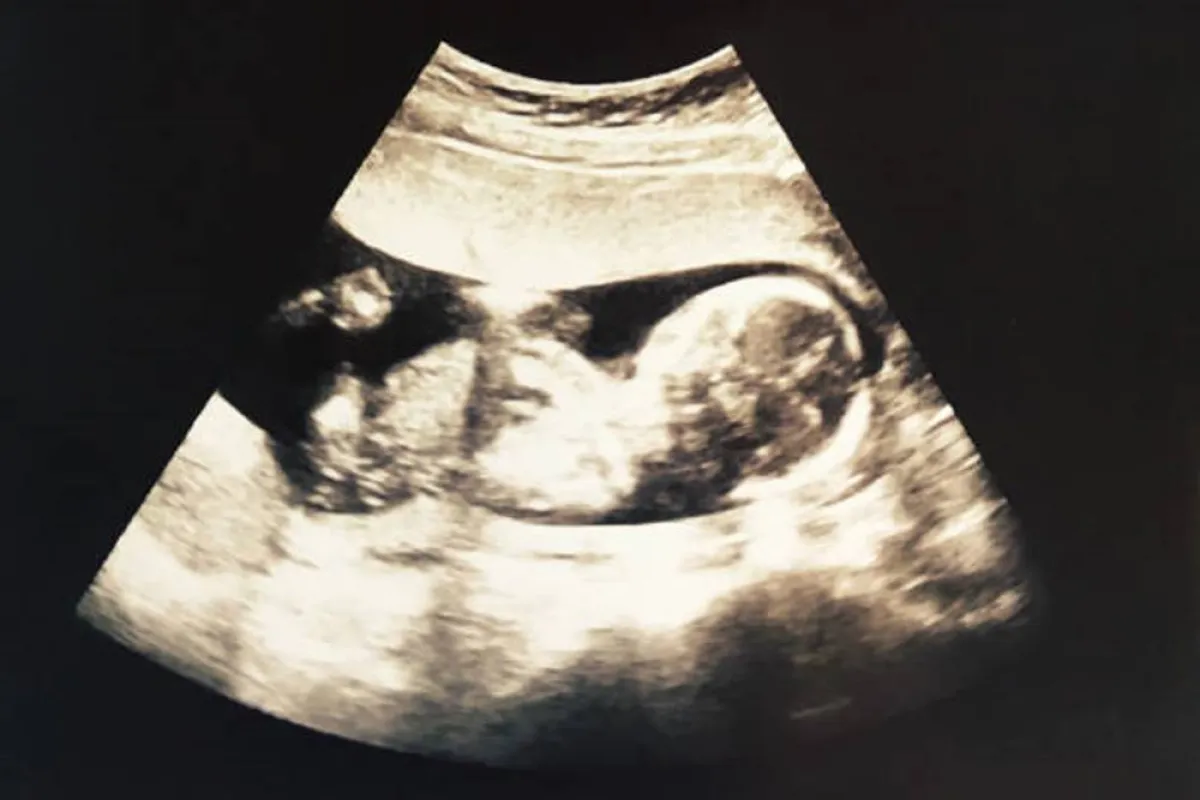

- هناك نساء حوامل يجرين تجربة مثيرة مع الجنين، حيث يتأكدن من خلالها أن جهازه العصبي ينمو بصورة سليمة وأنه قد أصبح يستشعر الضوء عن طريق القيام بتجربة سهلة.

- سوف تلاحظين أن الجنين يتحرك بسرعة ويتجه للمنطقة الثانية من البطن والسبب أن الضوء قد سبب له ضيقاً وابتعد عنه.

- ويقوم الجنين أيضاً باللعب بالحبل السري.